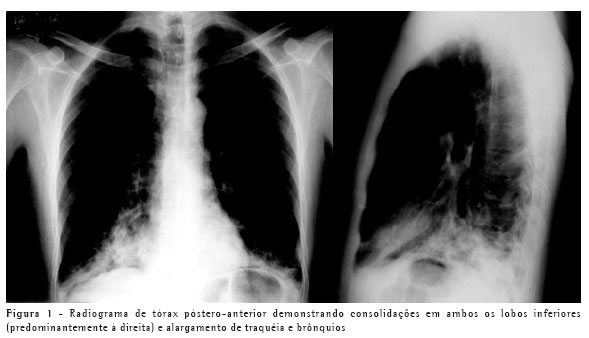

Poucos dias após o término do curso do tratamento com eritromicina, entretanto, o paciente voltou a apresentar tosse produtiva, associada a febre, e o radiograma não evidenciou melhora das consolidações. Foi novamente internado e realizou-se bacterioscopia de escarro, que evidenciou inúmeros polimorfonucleares e cocos gram-positivos em abundância. Cultura não era disponível. Iniciou tratamento com oxacilina intravenosa, obtendo resposta clínica satisfatória em poucos dias, motivo pelo qual foi iniciada a administração de cefalexina por via oral. Voltou a apresentar febre após 48h de uso de cefalexina via oral, o que motivou retorno para tratamento intravenoso e transferência para hospital de maior complexidade para investigação etiológica mais elaborada. O novo exame bacterioscópico de escarro neste momento evidenciou flora polimicrobiana e o paciente iniciou o uso de ceftriaxona associada a amicacina, com duração total de quatro semanas de tratamento, até a total resolução dos sintomas. Neste momento, foi realizada uma tomografia computadorizada de tórax, que demonstrou persistência das lesões consolidativas, de menor tamanho, em ambos os lobos inferiores, e confirmou o alargamento anormal da traquéia e brônquios principais (Figuras 1, 2 e 3), com bronquiectasias cilíndricas bilaterais nos lobos inferiores, caracterizando o diagnóstico de traqueobroncomegalia congênita, ou síndrome de Mounier-Kühn. As provas de função pulmonar evidenciaram aumento da capacidade pulmonar total (123% do previsto) e do volume residual (160% do previsto), sem outras alterações.

O diagnóstico pode geralmente ser feito utilizando-se apenas dados provenientes da radiologia convencional de tórax, através da mensuração do diâmetro traqueal, melhor visualizado na projeção em perfil. A tomografia computadorizada de tórax, entretanto, torna mais precisa essa mensuração. Os limites são 3 cm para diâmetro transverso da traquéia, e 2,4 cm e 2,3 cm para os diâmetros transversos dos brônquios principais direito e esquerdo, respectivamente. As provas de função pulmonar demonstram tipicamente aumento da capacidade pulmonar total à custa do volume residual, eventualmente com sinais de distúrbio ventilatório obstrutivo. Inexistem atualmente tratamentos específicos para esta condição além de antibioticoterapia durante as exacerbações e fisioterapia visando a auxiliar a eliminação de secreções, se houver. A utilização de próteses definitivas é reservada apenas para casos avançados selecionados, pois não existem indicações precisas.(5-6)